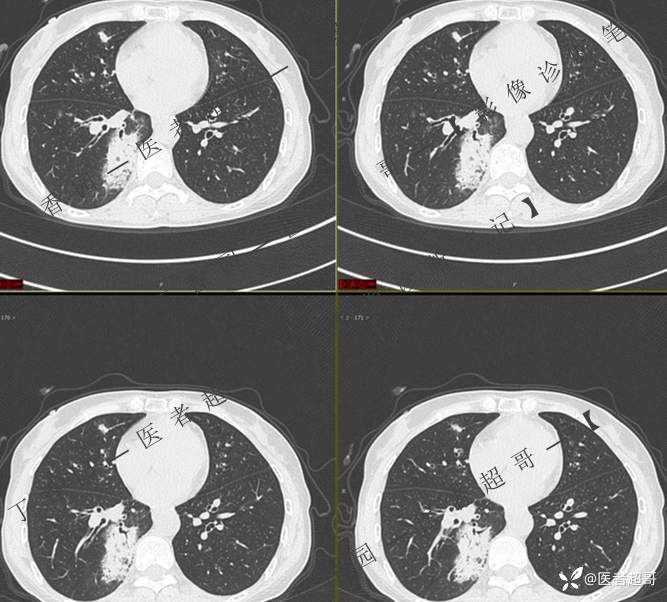

临床治疗一周后复查

第二次检查